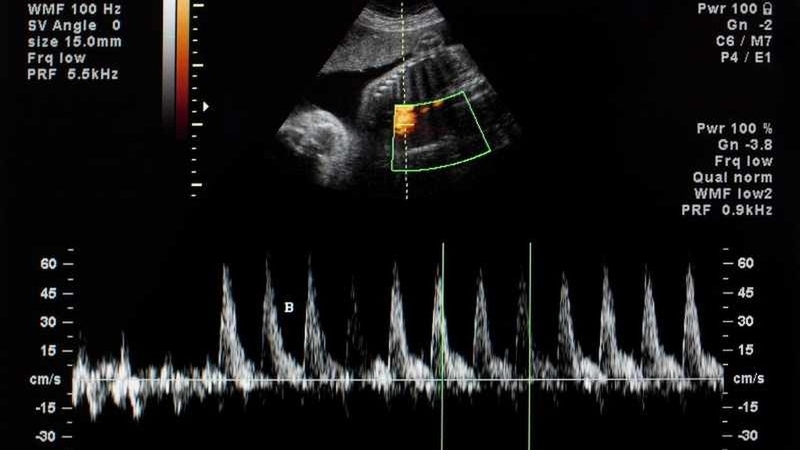

Nhịp tim của thai nhi không chỉ phản ánh sự phát triển của bé mà còn là phương pháp xác định giới tính được nhiều mẹ bầu áp dụng. Cụ thể, nếu nhịp tim thai đập trên 140 nhịp/phút thì có thể là bé gái. Ngược lại, nếu nhịp tim dưới 140 nhịp/phút thì đó có thể là dấu hiệu mang thai bé trai.

Vậy nhịp tim thai 158 lần/phút là trai hay gái? Từ sự khác biệt về nhịp tim giữa bé gái và bé trai có thể dự đoán rằng, nhịp tim thai ở mức 158 lần/phút nhiều khả năng là mẹ đang mang thai bé gái. Tỷ lệ chính xác cao nhất thường là ở tam cá nguyệt đầu tiên của thai kỳ. Qua giai đoạn này, nhịp tim của bé gái và trai bắt đầu ổn định, không có sự chênh lệch khác biệt nên độ chính xác sẽ giảm dần.

Thế nhưng, liệu quan niệm dựa vào nhịp tim để xác định giới tính thai nhi có chính xác không? Nhịp tim của thai nhi thường sẽ bắt đầu xuất hiện từ tuần thứ 6 của thai kỳ. Tuy nhiên, hiện tại vẫn chưa có căn cứ khoa học cụ thể nào về sự khác biệt của nhịp tim giữ bé gái và bé trai trong giai đoạn thai kỳ. Thông thường, nhịp tim sẽ tăng cao trong 3 tháng đầu và sẽ ổn định dần sau đó.

Tính từ tuần thứ 16 của thai kỳ, nhịp tim trung bình của thai nhi sẽ dao động từ 120 - 160 lần/phút và có thể đạt 180 lần/phút nếu thai nhi cử động nhiều. Theo các chuyên gia phụ sản, nhịp tim của thai nhi trong giai đoạn chuyển dạ cần được duy trì trong khoảng 110 - 160 lần/phút để đảm bảo tình trạng sức khỏe tốt nhất.